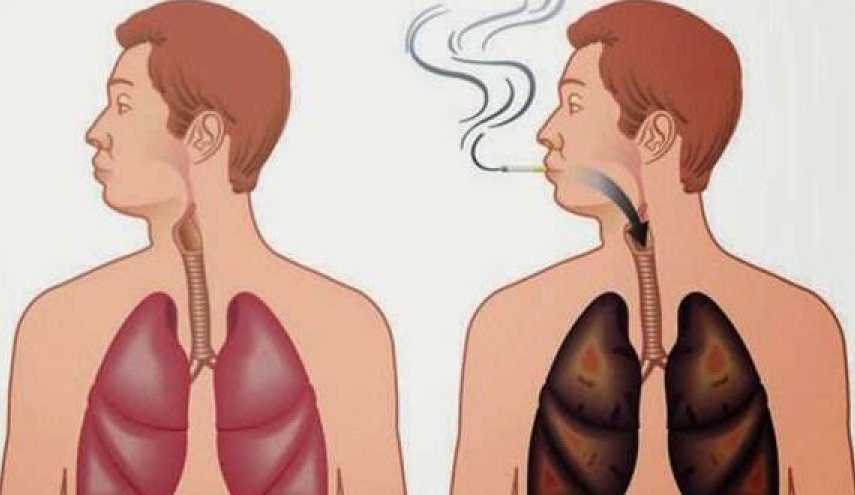

إذا استغرقت سنوات عدة في استنشاق دخان السجائر أو تعرضت بشكل متكرر لتلوث الهواء، أو تعاني مشكلات صحية تؤثر على الجهاز التنفسي كالربو والتكيس الرئوي، فقد يبدو تنظيف الرئتين أمرا غاية في الأهمية ومثيرًا لك، وهذا هو فحوى مقالنا، فتابعوا معنا.

رئتانا تفعل لنا الكثير؛ لذا فإن تنظيف وتطهير الرئتين أمر حيوي ويعود بمنافع كثيرة على الصحة العامة للإنسان، وهي عبارة عن أعضاء ذاتية التنظيف، تبدأ في تطهير نفسها فور توقف تعرضها للملوثات والسموم، فمثلًا إذا أقلعت عن التدخين مؤخرًا وبعد تعرض رئتيك لكم هائل من التلوث، ينتاب صدرك الاحتقان أو الالتهاب، لأن المخاط يتكون في الرئتين ليكون جميع الميكروبات ومسببات الأمراض الأمر الذي يساعد على الشعور بالثقل.

إذا علمت كم العواقب الوخيمة التي تجنيها من إثر اتباع هذه العادة السيئة ألا وهي التدخين، بما في ذلك تراكم كميات كبيرة من المخاط والسموم المتمركزة في الرئتين، أو زيادة فرص الإصابة بمرض الانسداد الرئوي المزمن، أو الموت المبكر، أو النوبات القلبية، أو سرطان الدم، لكان قرارك الأول والأخير هو الابتعاد نهائيًا عن الغازات السامة التي تطلقها سيجارة واحدة والتي تتخلل كل عضو في الجسم وتتلفه.